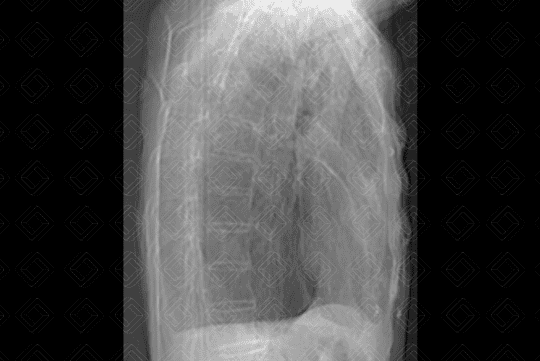

Descrição das figuras 1 e 2: Radiografia de tórax PA e perfil evidenciando os sinais clássicos de doença pulmonar obstrutiva crônica: diafragma retificado, coração alongado e verticalizado, além de aumento anteroposterior da caixa torácica.

• Radiografia de tórax: O r endimento da avaliação da DPOC pelo estudo radiológico simples é bastante limitado, não havendo anormalidade na radiografia se não existir aprisionamento de ar. Quando há aprisionamento de ar, os critérios mais seguros são: diafragma rebaixado ou retificado; aumento do espaço retroesternal (maior que 3 cm) e persistência do aumento do espaço retroesternal na expiração, coração alongado e verticalizado, presença de bolhas é inferida pela identificação de área de maior radiotransparência, avascular, podendo ou não estar delimitada por fina linha branca (figuras 1 e 2) ;